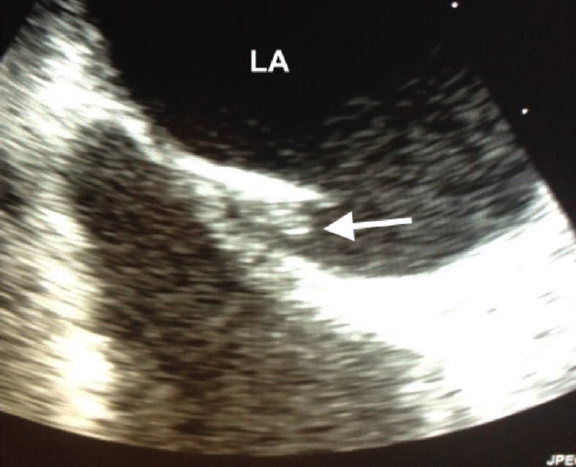

Since the original description of the LASP, there have been numerous studies confirming that thrombi can indeed form within the pouch.3,5 These studies include asymptomatic patients as well as individuals with recent thromboembolism. Figure 3 shows a transesophageal echo image of a young male who presented with a brachial artery thrombus.

(Courtesy Dr. Charles Searles, Emory University, Atlanta, Georgia).